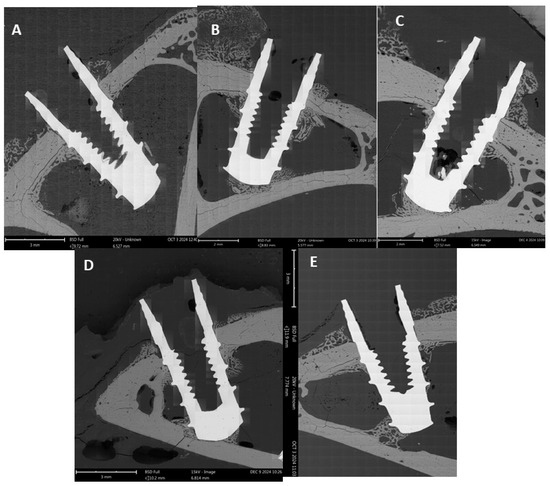

| Cooling Rate (°C/h) | BIC (%) Mean ± SD |

|---|---|

| Control (without treatment) | 37.5 ± 5.6 |

| 20 | 59.8 ± 7.0 * |

| 50 | 68.2 ± 5.2 * |

| 75 | 73.5 ± 9.0 * |

| 115 | 41.3 ± 9.2 |